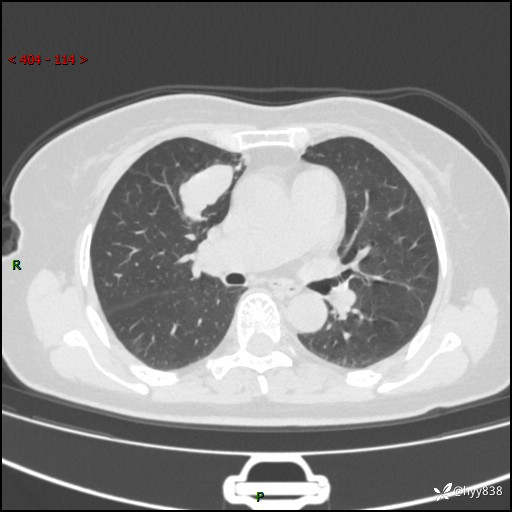

70岁/女,发现右上肺肿物10天。患者过敏体质,只有平扫,错过了一定可惜---结果公布~

【患者信息】:70岁/女

【主诉】:发现右上肺肿物10天

【现病史及既往史】:者10天前因“背部酸痛”于当地治疗,无发热,无呕吐,无头痛头晕等不适,胸部CT示右上肺肿物。遂来我科就诊,门诊看过病人后以“”收入我科, 自患病以来,精神、饮食、睡眠尚可,大小便正常,体力体重无明显减轻。

【检查】:胸部CT平扫(患者过敏体质,不能增强)